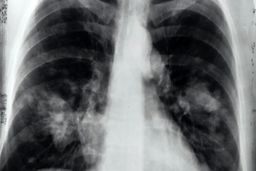

عفونت کرونا ویروس شدید در دو مرحله رخ میدهد

خبرمهم: سارس-کوو-۲ (SARS-CoV-۲)، ویروسی که باعث ایجاد بیماری کووید-۱۹ میشود، با ورود به مجاری تنفسی فرد و عفونت…

عامل آسیب ریه در اثر ابتلا به کووید ۱۹ شناسایی شد

خبرمهم: محققان دریافتند بقای سلولهای غیرطبیعی حاصل از ابتلا به کووید ۱۹ در ریه، مهمترین عامل بروز آسیبهای ریوی محسوب …